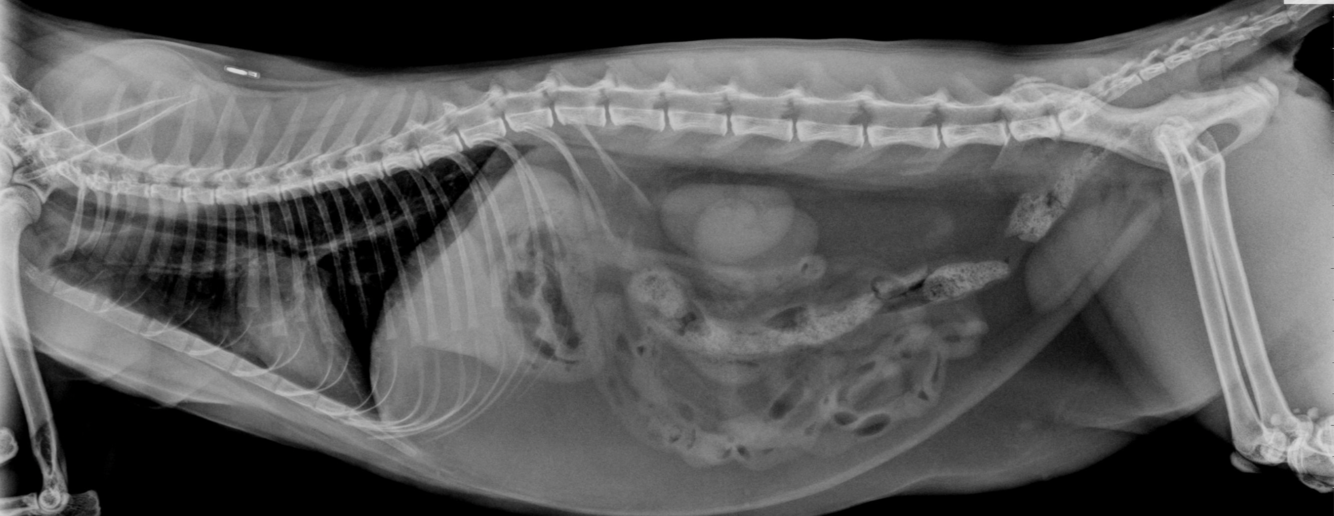

A five-year-old female spayed cat is presented with a two-day history of vomiting and anorexia.

Physical exam reveals 5% dehydration and abdominal discomfort. Plain abdominal radiographs are shown below.

Which choice is the most appropriate step to take next?

A - IV fluids and broad-spectrum antibiotics

B - Gastroduodenoscopy with biopsy

C - Exploratory laparotomy

D - Specific feline pancreatic-lipase assay

E - Non-iodinated contrast series

A